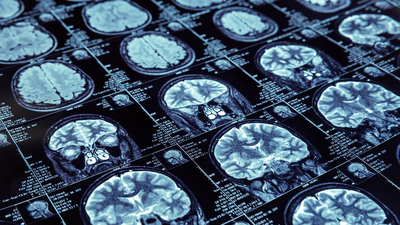

“Dünya Beyin Cerrahisi Dernekleri Federasyonu” Onursal Başkanı Prof. Dr. Uğur Türe, beynin farklı bölgelerindeki lezyonların başarılı biçimde çıkartılabilmesi için geliştirdiği farklı ameliyat teknikleriyle alanındaki en saygın dergi konumundaki “Journal of Neurosurgery” dergisinde bir kez daha kapak konusu oldu.

İlk kez Kasım 2004'de aynı derginin kapağında Hocası Profesör Gazi Yaşargil ile birlikte yer alan Dr. Türe, Mayıs 2016 ve daha sonra da Ağustos 2021’de geliştirdiği yeni ameliyat teknikleriyle kapak konusu olmayı başarmıştı. Son olarak Ocak 2024 sayısının kapağıyla da dördüncü kez beyin ve sinirbilim alanının ‘en önemli’ yayınının kapak makalesine imza atmış oldu.

Yeditepe Üniversitesi Tıp Fakültesi Beyin ve Sinir Cerrahisi Anabilim Dalı Başkan Prof. Dr. Uğur Türe kendi geliştirdiği ve bilim dergisinin Ocak 2024 kapak konusu olan yeni cerrahi teknikle çok önemli bir yenilik ortaya koyuyor.

“Daha önce beyin ve beyincik arasından yapılan ameliyatlar sırasında o bölgedeki toplar damarlar yakılıyordu ve bu, hastanın iyileşme sürecine olumsuz etki edebiliyordu” diyen Prof. Dr. Türe, ameliyat edilen bölgedeki damarları alışılageldiği gibi yakmak yerine koruyarak beyne zarar vermeden müdahale etmenin bir yolunu buldu. Böylece hem damarlar zarar görmeden korunmuş oluyor hem de ameliyat sonrasında gelişebilecek komplikasyonlar minimuma iniyor.

Prof. Dr. Türe, yeni tekniğini önce laboratuvarında, sonra da ameliyatlarında kullanarak mükemmelleştirdi. Böylece hem hastalarının beyinlerinin daha az zarar görmesini sağladı hem de ameliyat sonrası iyileşme hızlarını artırarak tüm dünyada büyük yankı uyandırdı.